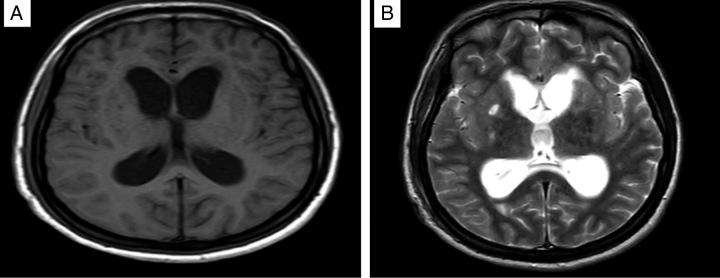

The 15-year-old female patient was admitted to the hospital with altered mental status after complaining of nausea, weakness, and cough for 3 weeks. A chest computed tomography (CT) scan showed cavitary lesions, a lumbar puncture sample had a glucose level of 15 mg/dl, and the brain CT scan revealed acute hydrocephalus. While the patient was treated with anti-tubercular medications, an external ventricular drain was placed and the patient was monitored.

一名15岁女性患者在诉说恶心、乏力和咳嗽3周后因精神状态改变入院。胸部计算机断层扫描(CT)显示有空洞性病变,腰椎穿刺样本葡萄糖水平为15毫克/分升,脑部CT扫描显示有急性脑积水。在患者接受抗结核药物治疗时,放置了外部脑室引流管并对患者进行监测。